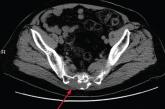

78-year-old man • tail bone pain • unintended weight loss • history of diabetes and hypertension • Dx?

► Tail bone pain

► Unintended weight loss

► History of diabetes and hypertension